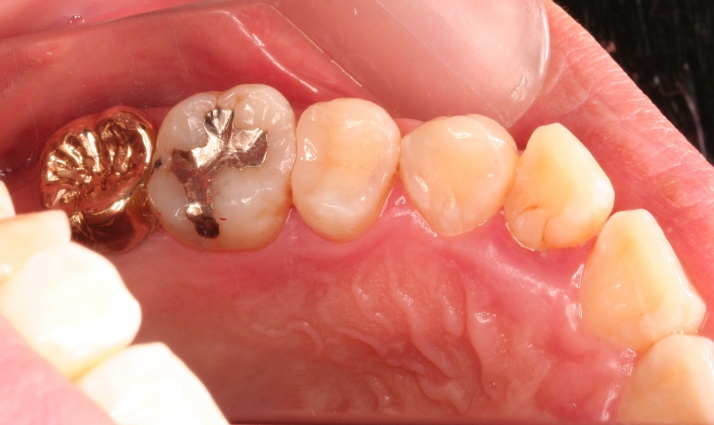

メタルセラミックス修復

担当歯科医師:川津良介理事長

2013年5月3日平成25年5月2日 千葉市中央区 H.S様 右下67番 メタルボンドクラウン修復